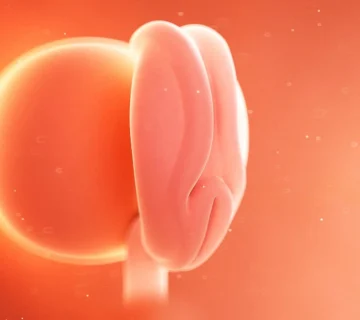

👧👦 تفاوتهای جنسی در هفته یازدهم بارداری

اگر جنین شما دختر باشد، اکنون تخمدانهایش شکل گرفتهاند.

اگر پسر باشد، بیضهها و کیسه بیضه در حال تشکیل هستند.

با این حال، هنوز برای تشخیص جنسیت جنین با سونوگرافی کمی زود است و معمولاً در هفتههای ۱۴ تا ۱۶ امکانپذیر میشود.